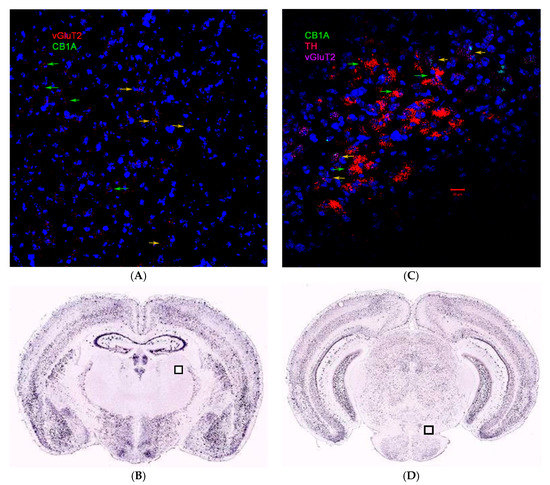

2.3. CB1R and CB2R Cannabinoidergic Neurons